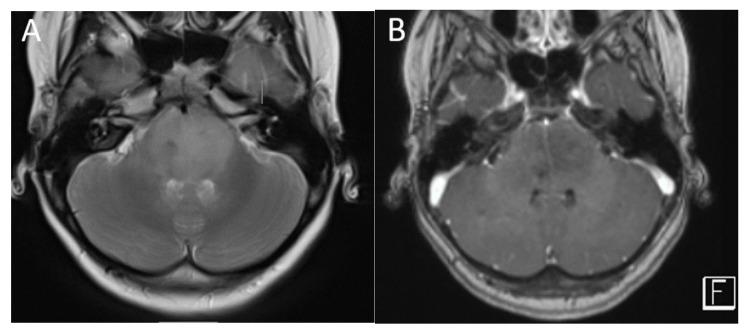

Primary brain tumors are the most common solid neoplasms in children and a leading cause of mortality in this population. MRI plays a central role in the diagnosis, characterization, treatment planning, and disease surveillance of intracranial tumors. The purpose of this review is to provide an overview of imaging methodology, including conventional and advanced MRI techniques, and illustrate the MRI appearances of common pediatric brain tumors.

原发性脑肿瘤是儿童中最常见的实体肿瘤,也是该人群死亡的主要原因。磁共振成像(MRI)在颅内肿瘤的诊断、特征描述、治疗规划和疾病监测中起着核心作用。本综述的目的是概述成像方法,包括传统和先进的MRI技术,并阐述常见儿童脑肿瘤的MRI表现。